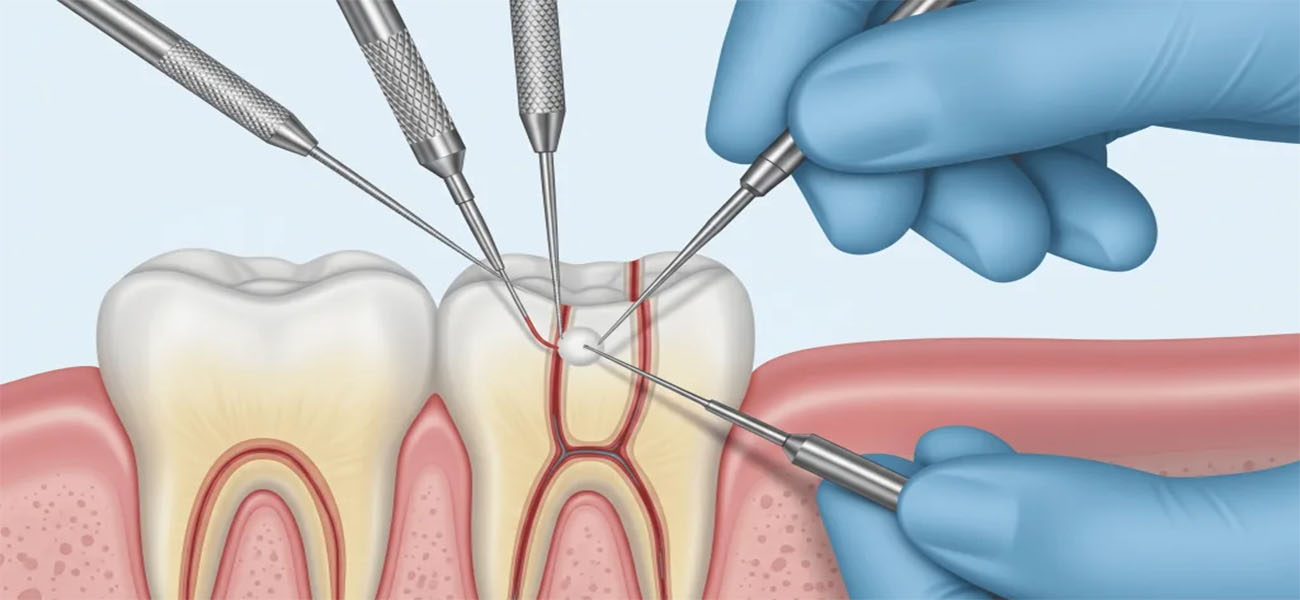

عصب کشی دندان (اندودنتیک) یک روش درمانی است که برای نجات دندانهای آسیب دیده یا عفونی شده انجام میشود. این روش شامل حذف بافت ملتهب یا عفونی از داخل دندان و پر کردن آن با مواد مخصوص است. عصب کشی به دلایل زیر اهمیت دارد:

در مرحله اول، پزشک وضعیت دندان آسیب دیده را بررسی کرده و با استفاده از تصاویر رادیوگرافی، عمق آسیب را تعیین میکند.

2. بی حسی موضعی

پس از تأیید نیاز به عصب کشی، پزشک ناحیه مورد نظر را با بی حسی موضعی بی حس میکند تا بیمار در طول درمان احساس درد نکند.

3. حذف بافت آسیب دیده

در این مرحله، پزشک با استفاده از ابزارهای مخصوص، بافت ملتهب یا عفونی داخل دندان را حذف میکند.

4. پاکسازی و فرم دهی کانال ریشه

پس از حذف بافت آسیب دیده، کانال ریشه دندان تمیز و فرم دهی میشود تا آماده پر کردن باشد.

5. پر کردن کانال ریشه

در نهایت، کانال ریشه با مواد مخصوص پر شده و دندان ترمیم میشود.